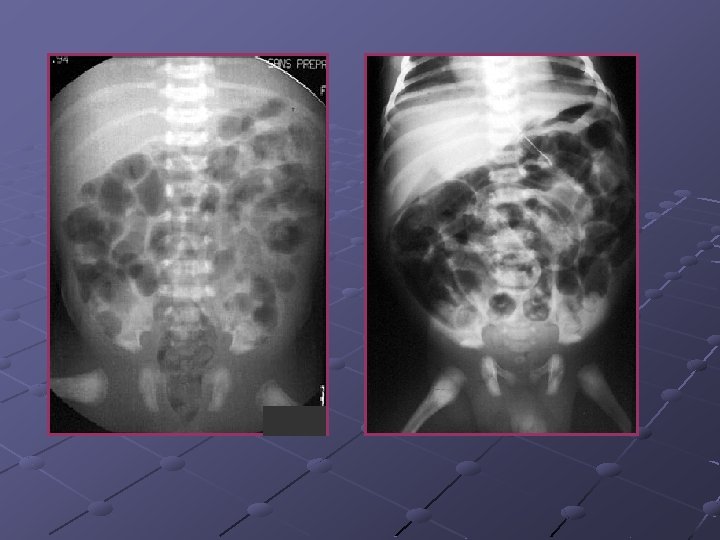

Cas n° 3 Garçon de 19 ans Pas d’antécédents particuliers Douleurs et distension abdominales, vomissements Examen distension diffuse, pas de signes de péritonite

« northern exposure sign » « coffee bean sign »

Volvulus du colon sigmoïde Cause fréquente de volvulus( segment long et mobile) ASP couché ( « coffee bean sign » ) pose le diagnostic dans 80% des cas Origine congénitale ou défaillance des moyens de fixité du colon ttt: décompression endoscopique suivie d’une résection élective